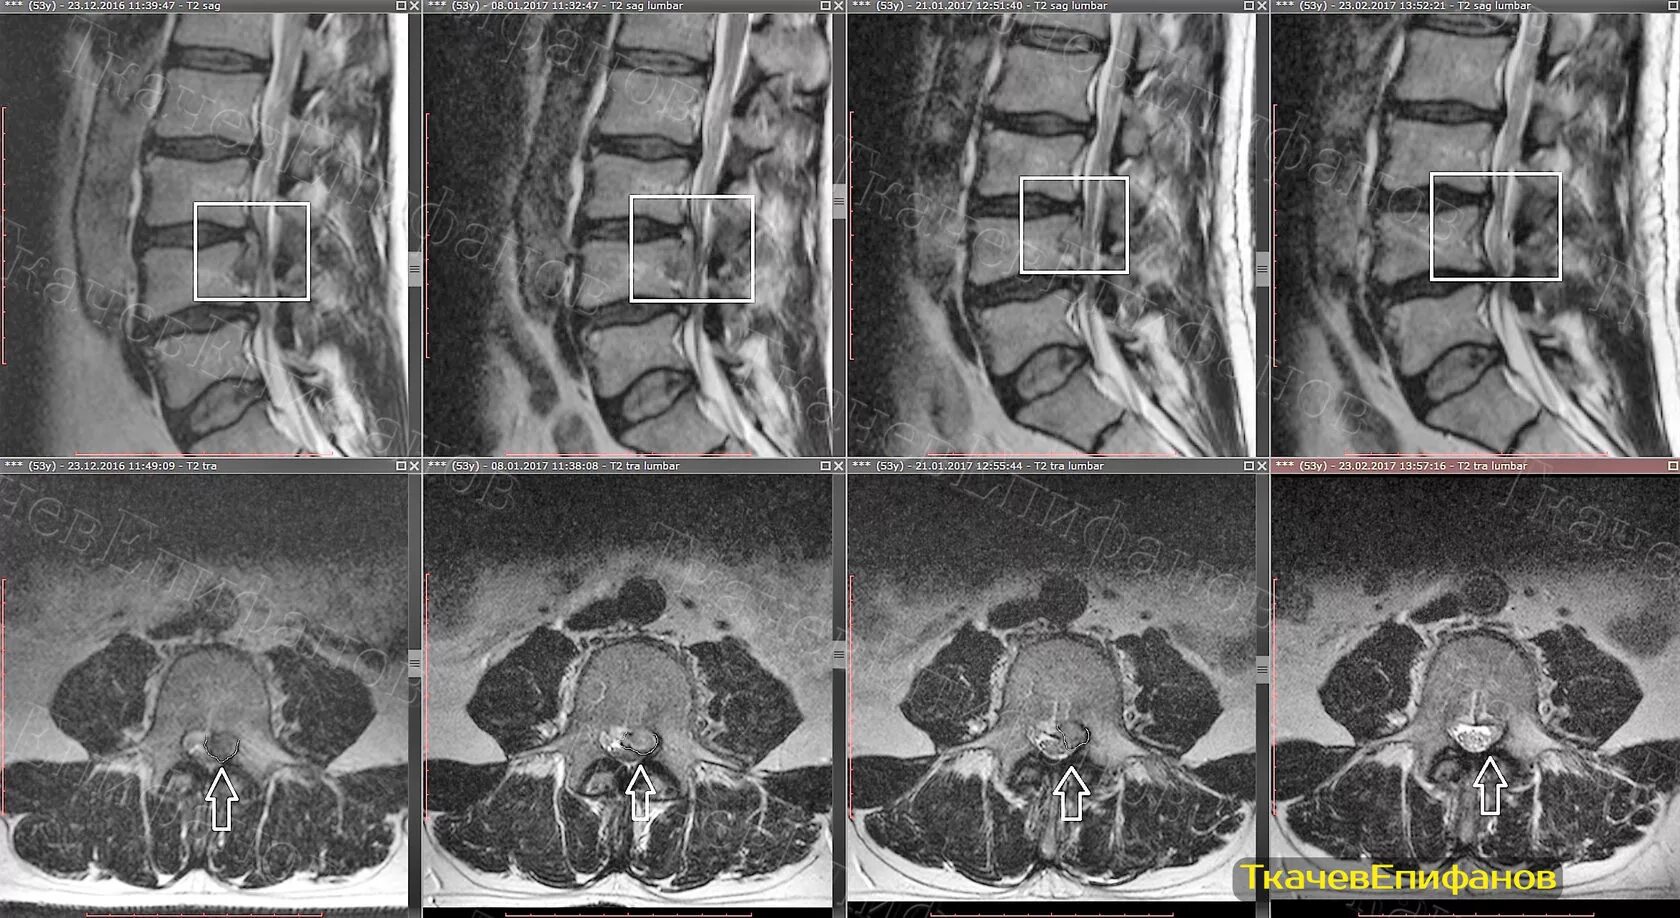

Дегенеративные изменения диска l5 s1